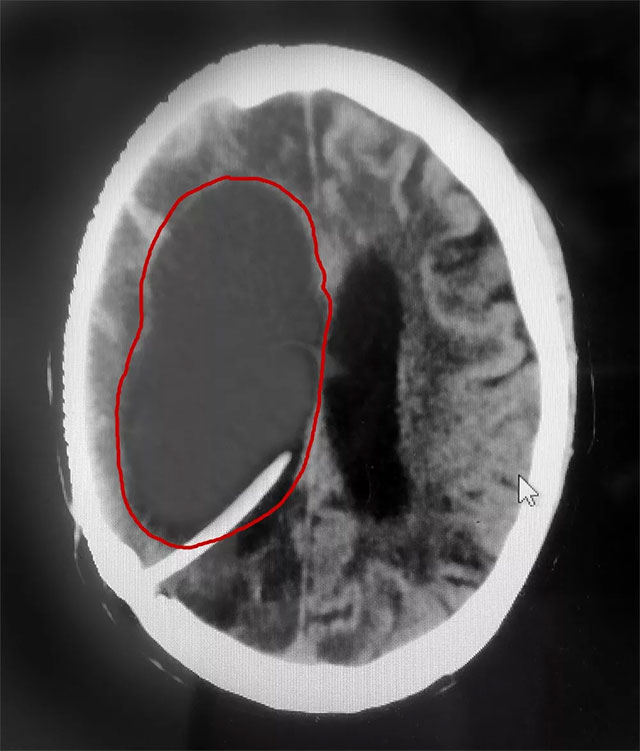

近日,上海蓝十字脑科医院神经外科6A病区收治了一位重度脑积水患者。三年前,患者金某(化名)因右侧大脑中动脉瘤破裂昏迷,在外院进行了开颅动脉瘤夹闭术和颅内血肿清除术。术后,由于伤口感染等原因,出现了脑脓肿、脑积水等并发症,长期处于昏迷状态。

在完善相关检查后,患者重度脑积水明确,若不及时治疗可能危及生命。

▲ 患者右侧脑室重度脑积水被及时置管分流